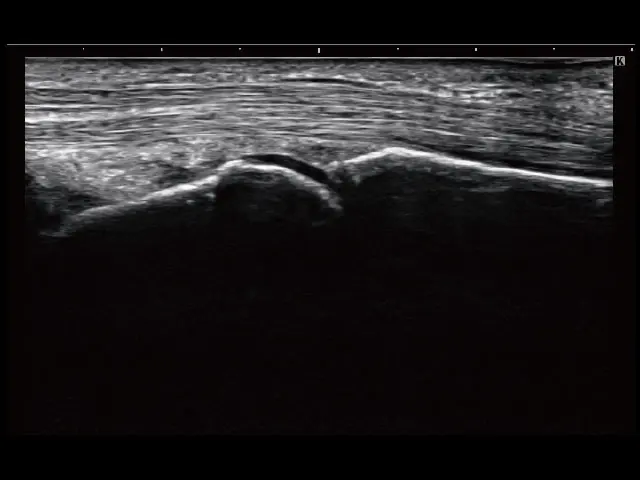

イメージギャラリー

イメージ画像を表示する